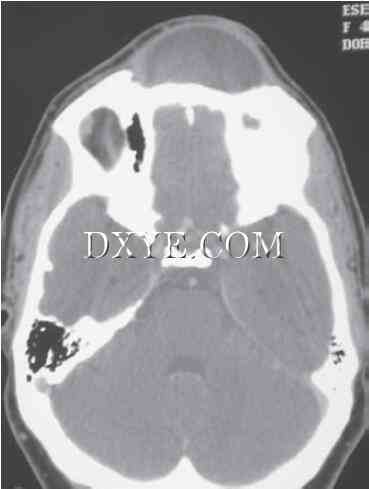

2.jpg

图29.2.  骨折漏由Panorex。A. 下颌骨在全景片上显示正常。B. 同一病人显示完全骨折的CT扫描。虽然全景X光片提供了关于下颌骨和牙列的有价值的信息,但图像中的扭曲可以掩盖骨折。